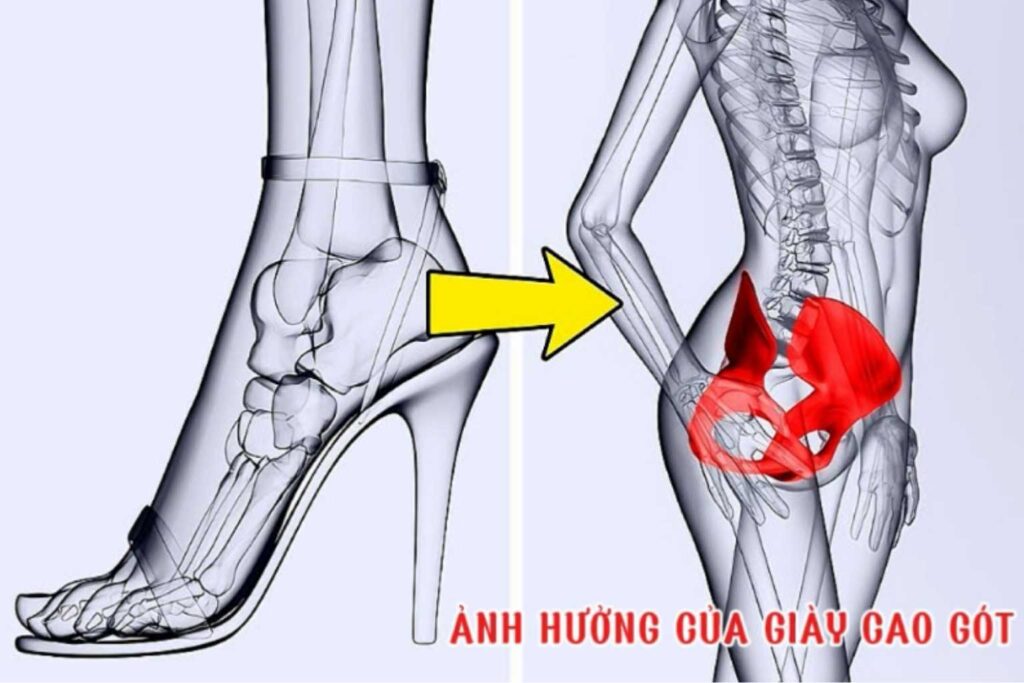

Ít ai ngờ rằng, đôi giày chúng ta mang hàng ngày lại là một trong những nguyên nhân thầm lặng gây đau lưng. Việc lựa chọn sai giày, đặc biệt là giày cao gót, có thể ảnh hưởng nghiêm trọng đến sức khỏe cột sống. Hãy cùng tìm hiểu mối liên hệ này và khám […]